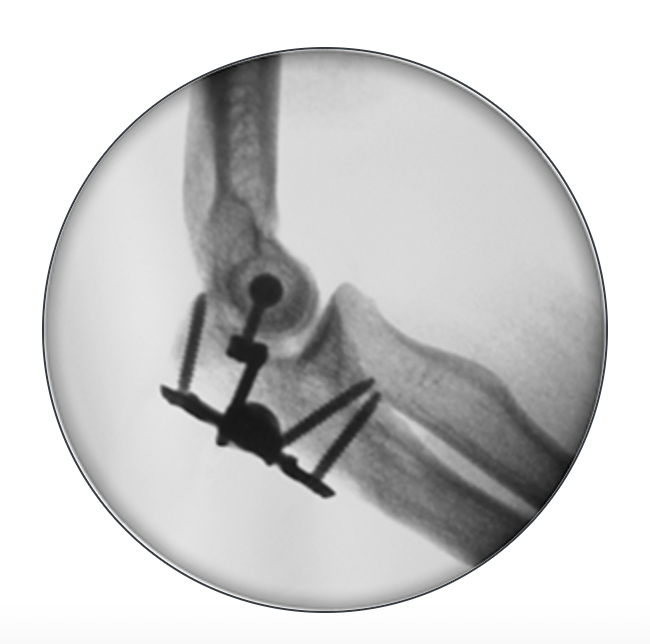

Fixed external fixation

AO surgery reference fixed external fixation

Lateral humeral pin | Ulna pins |

---|---|

Anterior to radial nerve

|

Subcutaneous border of ulna